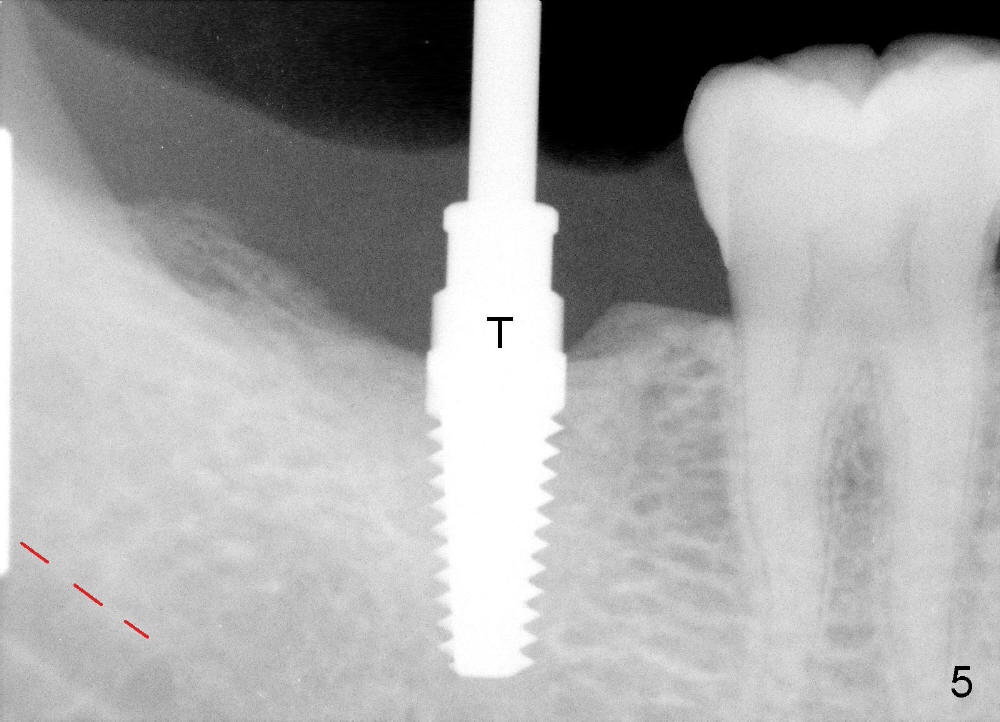

Infiltration anesthesia is administered with 68 mg of Septocaine, 34 mg of Lidocaine, 34 mcg of Epinephrine around the site of the lower right 2nd molar. An incision is made. A 2 mm pilot drill is used to initiate osteotomy at the depth of 8 mm. A parallel pin is inserted for the 1st intraop PA (Fig.4: P), which shows once more time the likelihood of incooperation from the patient. Combined with the information from CT, it appears alright to continue increasing osteotomy in the diameter and depth until 5x11 mm (Fig.5,6 (T: tap)). A 6x14 mm tap is inserted at 11 mm in bone. When the tap is removed, an explorer is used to check the intrigity of the osteotomy walls. No vibration is palpated linguoapically during drilling and inserting taps. There is no abnormal hemorrhage from the osteotomy. Finally 6x14 mm implant is placed as expected (Fig.7). The wound is healing 6 days postop (Fig.8).